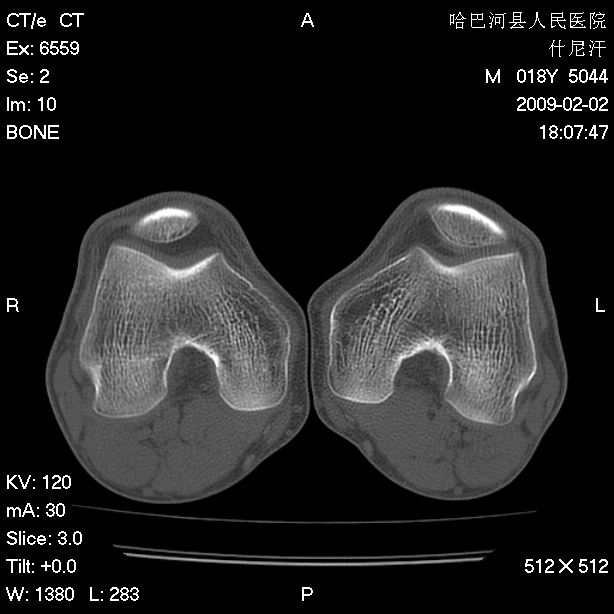

标题: CT17889:外伤后右膝关节反复疼痛3年余 [打印本页]

标题: CT17889:外伤后右膝关节反复疼痛3年余

ct未见明显异常。关节腔未见明显积液,半月板未见明显撕裂。但最好还是mri看看韧带及半月板情况。